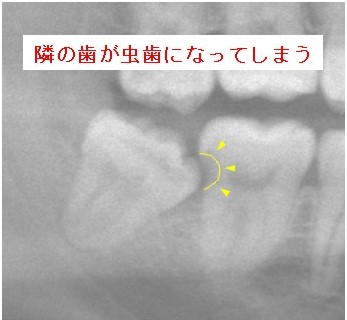

②隣の歯が虫歯になってしまう

などのいろいろな可能性がありますが、②③のように隣の歯に悪影響を及ぼしてしまうことが一番心配です。

親知らずをもっと早くに抜いておけば、隣の歯を削らなくてすんだのに、抜かなくてすんだのに、といった症例によく出会います。